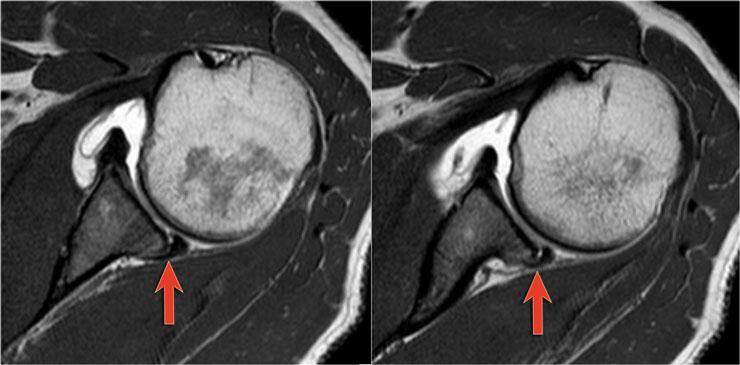

Có hình ảnh bong tách sụn viền trước-dưới (vị trí 3-6 giờ) với rách hoàn toàn màng xương bả vai phía trước.

Mũi tên chỉ vào màng xương bị gián đoạn.

Trên MRI khớp cản từ, sụn viền vắng mặt ở phía trước ổ chảo và mảnh sụn viền bị di lệch ra trước (mũi tên).

Có tổn thương Bankart xương (mũi tên đỏ cong).

Đường rách lan lên trên (mũi tên đen).

Ngoài ra còn có khuyết Hill-Sachs (mũi tên đỏ).

Hình MRI khớp cản từ mặt phẳng đứng dọc cho thấy sự lan rộng lên trên của đường rách Bankart.